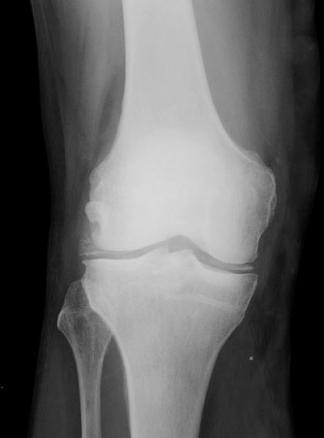

© La Revue du Praticien Radiographie du genou droit de face. Chondrocalcinose articulaire. Incrustation calcique des ménisques.